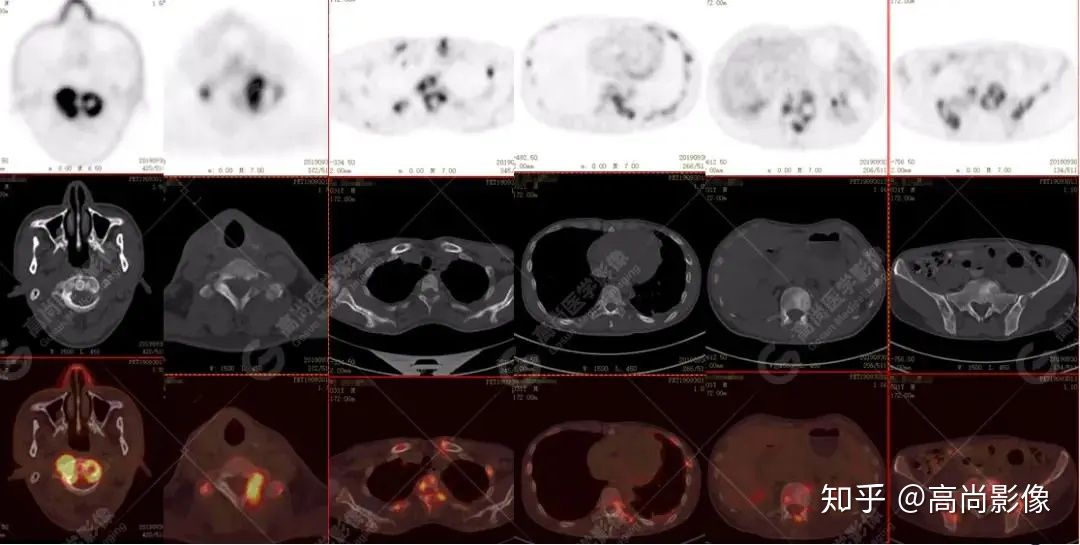

全身多發(fā)高代謝腫大淋巴結(jié),中央代謝缺損

左肺上葉尖后段及下葉背段多發(fā)簇狀斑點(diǎn)狀高代謝灶

左側(cè)胸膜結(jié)節(jié)樣增厚,代謝不同程度增高

【PET/CT提示】雙肺、左側(cè)胸膜多發(fā)結(jié)節(jié)影,全身多處骨質(zhì)破壞,全身多發(fā)淋巴結(jié)腫大,代謝攝取不均勻性增高。

特征:肺部病灶簇狀分布,上葉尖段及下葉背段為著;腫大淋巴結(jié)分布不對稱,無融合、中央有壞死改變,與淋巴瘤、轉(zhuǎn)移瘤等有一定的鑒別診斷意義;